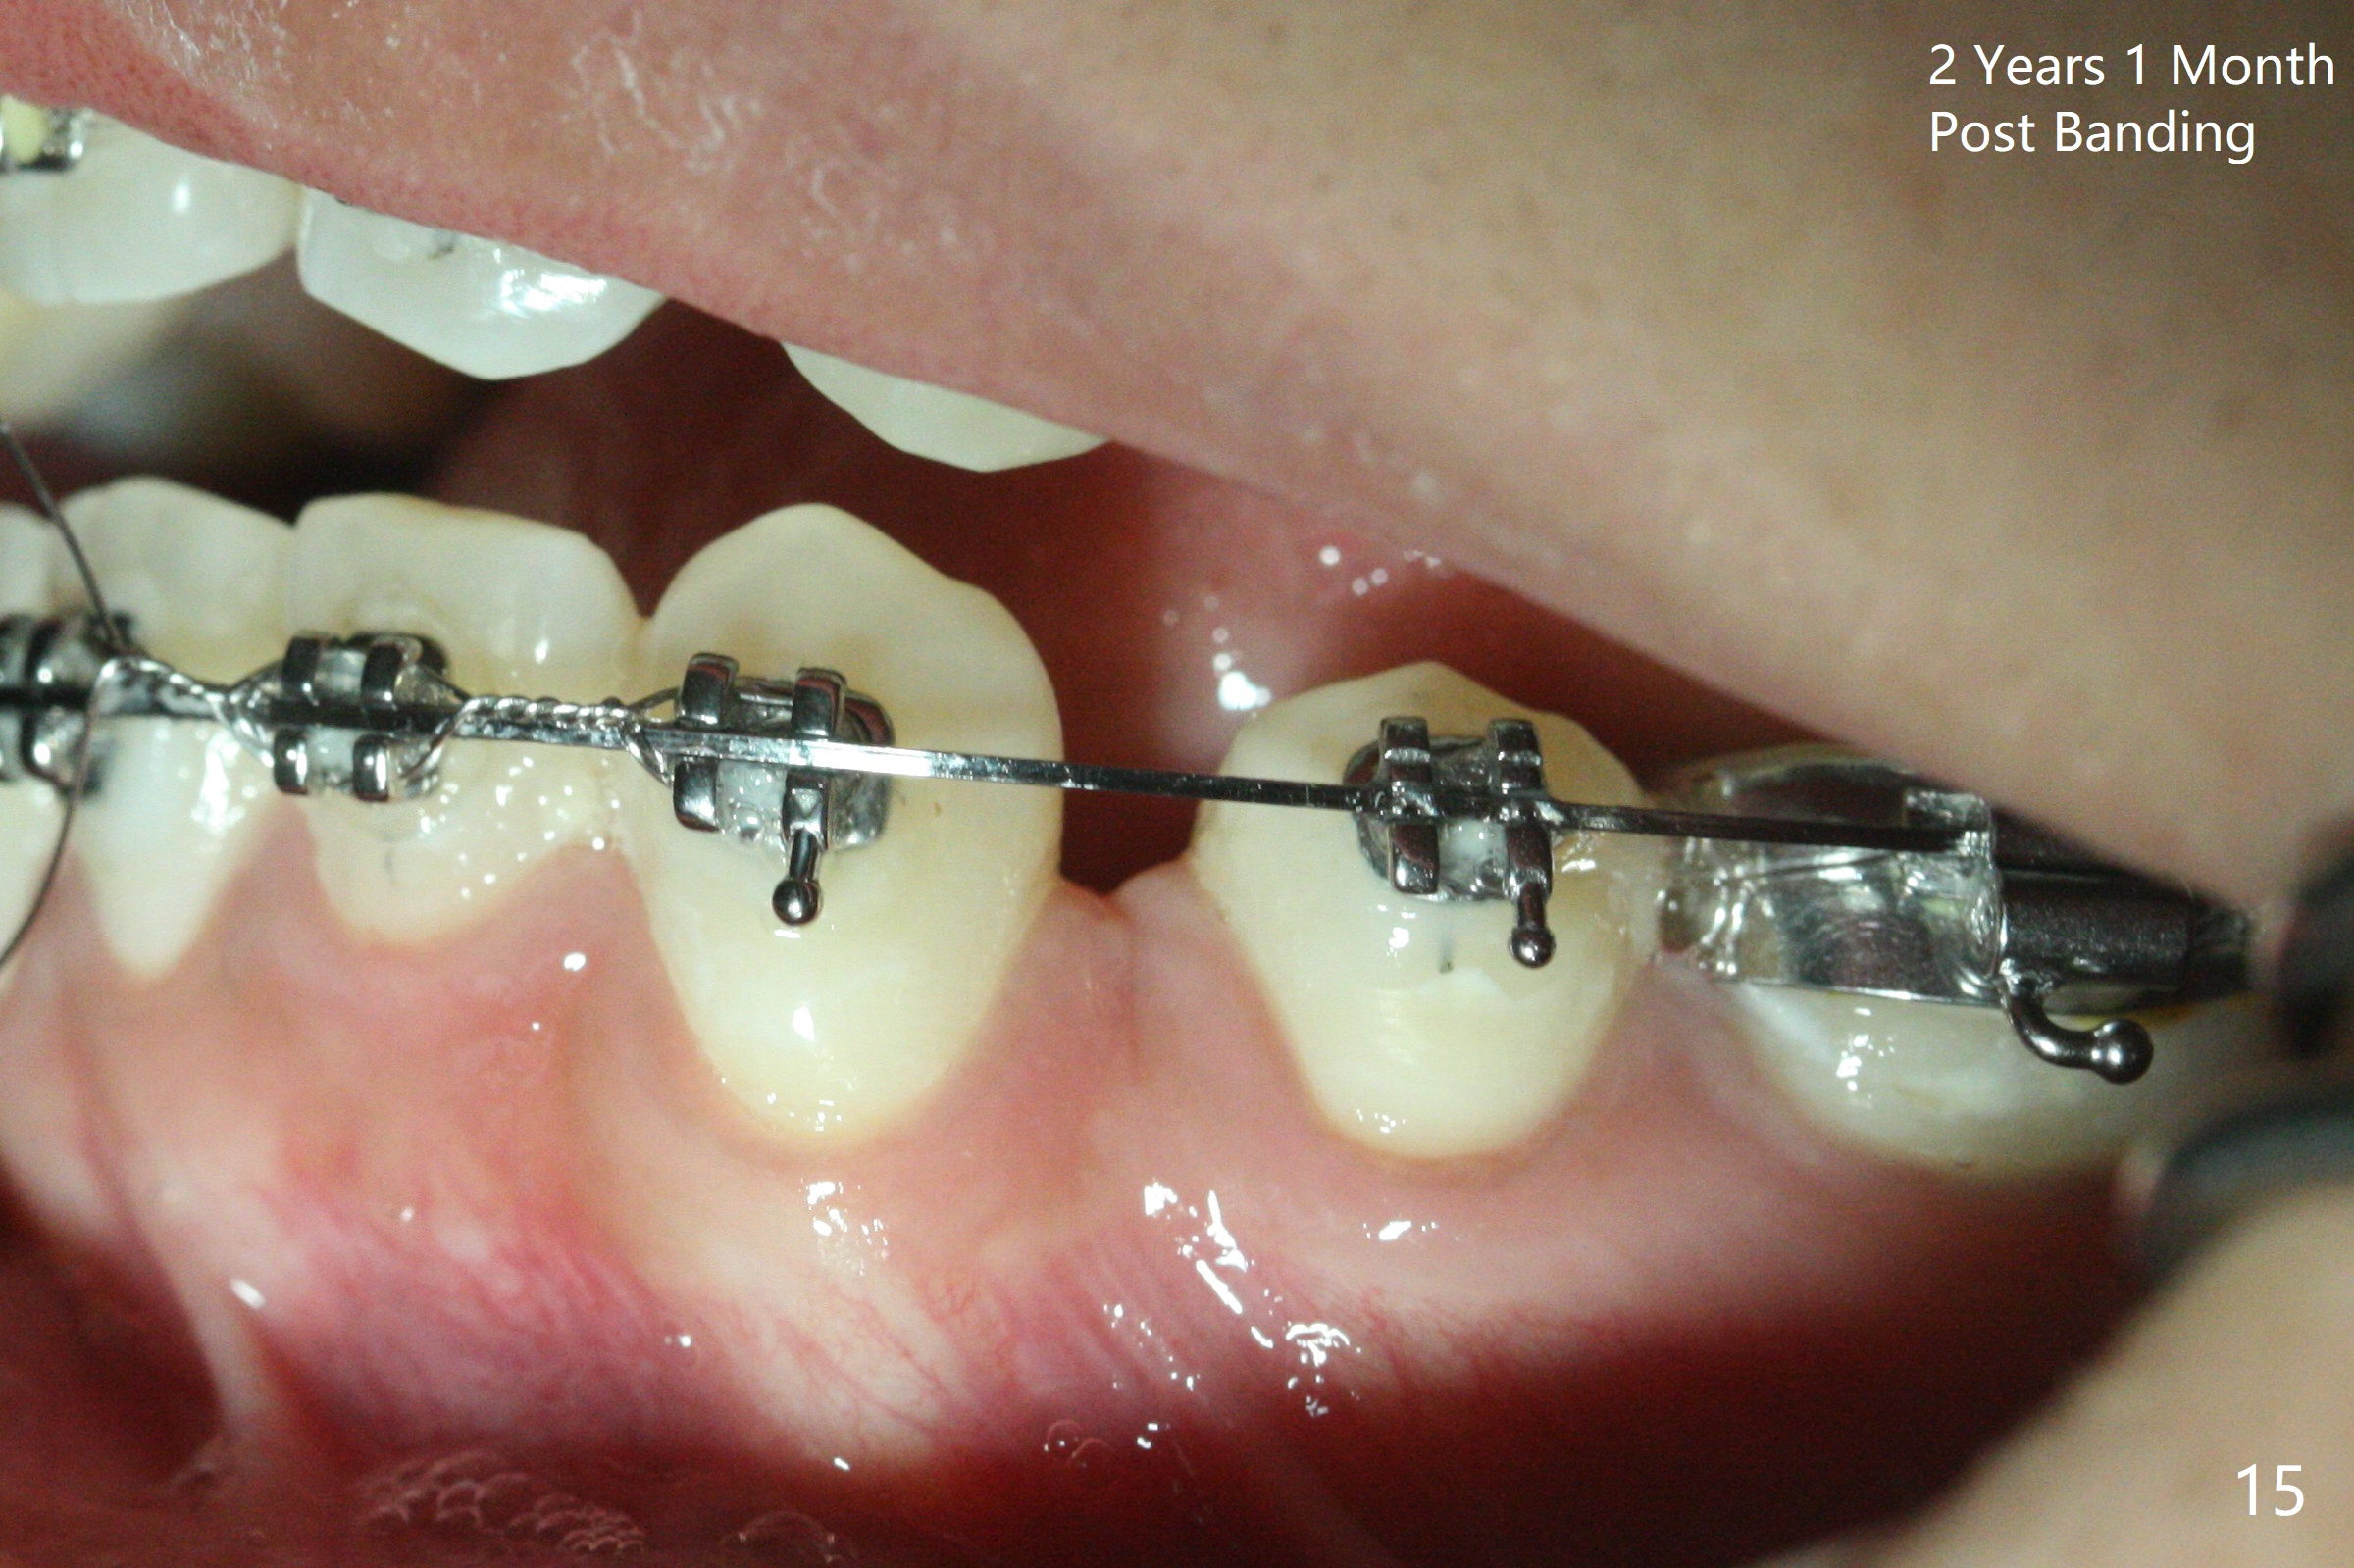

Thirteen months post banding, U dental midline apparently coincides with facial one, diastemata: UL2/3, UL6/7, L3-3, UL post detached, placed crimpable mini post mesial to UL2, closed spring UL2-7. Three-4 weeks later, diastema appears between UL1/2, while that of UL6/7 closes. Continue closed spring between UL2/7, while adding power chains U2-2 (Fig.12). To correct anterior overjet (Fig.13), Class II retraction is introduced bilaterally (Fig.14). After mesialization of LL3 (with Class I canine occlusion), L3-3 are being ligated as an anchor to mesialize LL5 (Fig.15). Occlusion appears to be Class II nearly 3 years post banding. Miniimplants are planned to distalize the upper dentition. Upper anterior PAs are taken to determine whether the roots of the upper anterior teeth have been resorbed. In fact, they are (Fig.16,17). Fortunately the anterior overjet does not look so severe. Orthodontic treatment should be terminated soon. Next case PAs should be taken prior to distalization.